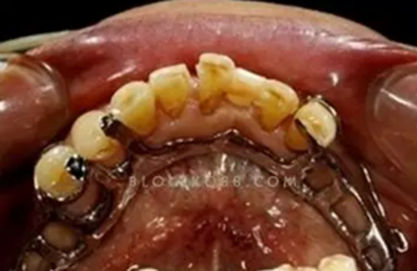

為了方便大家討論,圖片一一編號。

(圖1,引自劉亮大夫,非常經(jīng)典的Kennedy2類力學設計方案)

(圖2,4頰側(cè)的固位臂純粹是多余)